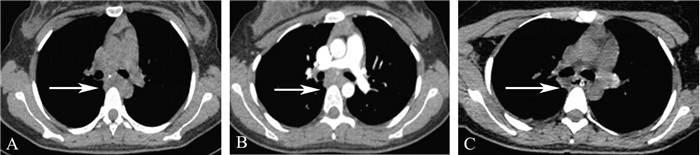

病例报告 一、病例资料患者女,20岁。因“吞咽困难1个月余”于2018年1月28日入院,既往无肺结核病史,家族中无结核感染病史。体格检查:体温36.5 ℃,心率98次/分,呼吸18次/分,血压112/86 mm Hg (1 mm Hg=0.133 kPa),双肺呼吸运动均匀对称,语音震颤未见明显增强或减弱,叩诊呈清音双肺未闻及明显湿啰音及胸膜摩擦音,腹部查体未见异常。辅助检查:普通胃镜检查提示距门齿25 cm处可见一大小约2.1 cm×2.3 cm的黏膜隆起,表面光滑;考虑为:黏膜下来源?外压?(图 1A)。经电子胃镜超声示黏膜肌层中低回声团块,表面黏膜完整,考虑黏膜下来源,平滑肌瘤可能(图 1B)。胸部CT平扫示纵隔内气管隆突下方软组织肿块影,大小约2.7 cm×2.8 cm,其内可见钙化影,与邻近食管分界欠清,性质?(图 2A)。胸部增强CT示气管隆突下方见一大小约为2.9 cm×2.6 cm的软组织肿块影,可见部分钙化影,边界不清,增强扫描呈轻度强化,考虑为:增大淋巴结?(图 2B)。上消化道钡剂造影示黏膜规则,管壁光滑柔软,未见异常病变。入院后行血液分析、肝肾功能均未见异常,痰涂片未见结核杆菌,ESR正常,结核抗体试验阴性。

图 2 食管结核患者胸部CT图 A:胸部CT平扫示气管隆突下方软组织肿块,边界不清(箭头);B:胸部增强CT示气管隆突下软组织肿块,边界模糊,呈轻度强化(箭头);C:术后软组织肿块明显缩小(箭头) |

患者术后第2日复查胸部CT示食管下段壁稍增厚、模糊,周围脂肪间隙模糊;双肺未见明显钙化灶(图 2C),予以拔除右侧纵隔引流管;复查上消化道钡剂造影示:黏膜光滑规则。术后第3日予以拔除胃管,同时嘱患者开始进少渣流食。术后病理检查结果示(隆突下肿块)肉芽肿性炎,伴灶性区域凝固性坏死及巨细胞反应,镜下组织形态考虑结核(图 3A~C)。术后行结核感染T细胞检测结果阳性,抗原A斑点数168个,抗原B斑点数>300个;遂即给予患者行抗结核治疗(异烟肼0.3 g+利福平0.45g+乙胺丁醇0.75 g+盐酸左氧氟沙星0.5 g,以上药物均每日1次)。患者术后第10日复查肝肾功能未见异常,带口服药出院治疗。2个月后电话回访,患者吞咽困难等症状完全缓解。